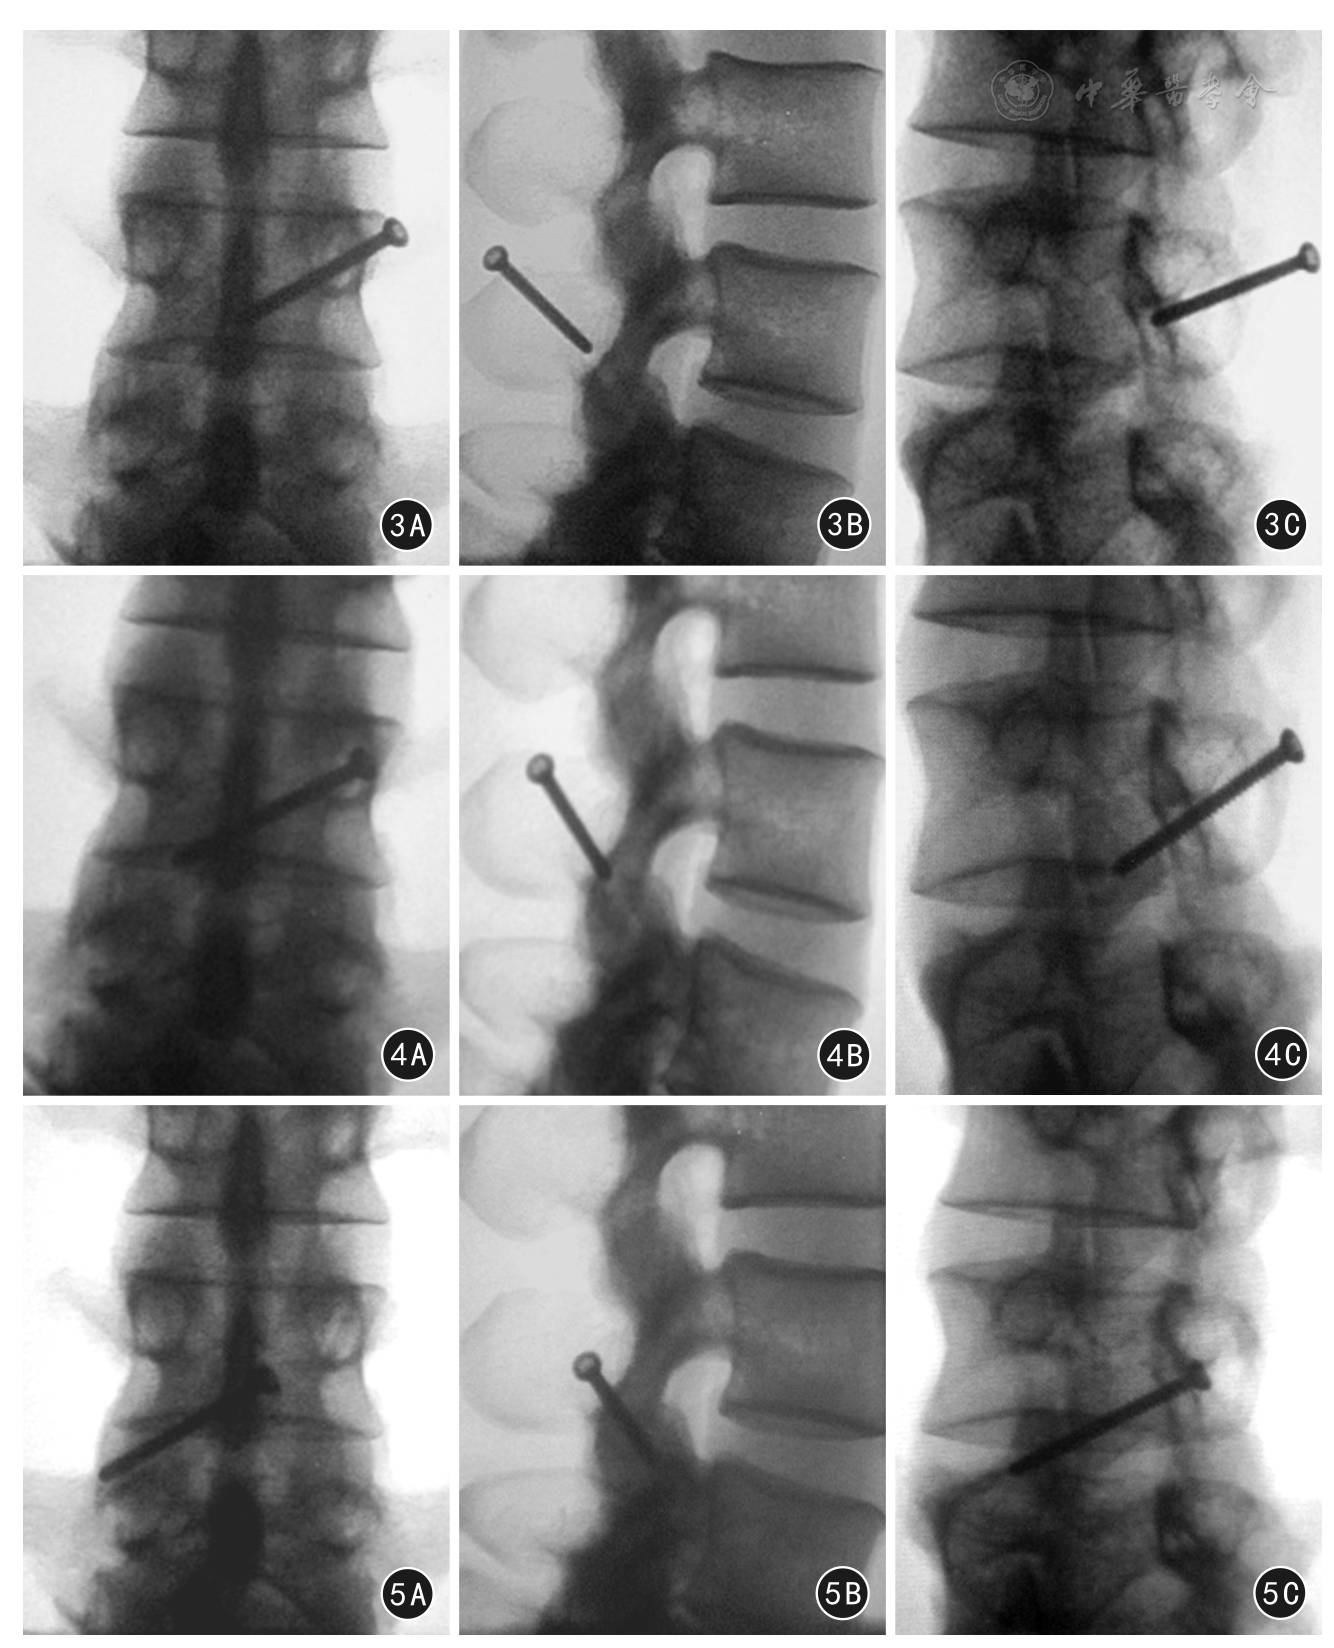

截取L2~S1节段脊柱,剔除脊柱周围的肌肉组织,显露椎板、关节突、横突基底等后柱结构,保留韧带及小关节囊、椎间盘及骨性结构的完整。按照文献[11]描述的方法,直视下L3/4、L4/5、L5/S1完全随机单侧置入直径4 mm螺钉。进钉点选择在一侧椎板与棘突交界中下1/3处向后约0.5 cm。外倾角[12]的确定是在术前横断位CT片上测量,这个角度和椎板的角度是一致的。、,、,两线的夹角即为外倾角(图1)。下倾角[12]可以由术前正位X线片上测量得到,画一条经过椎板棘突结合部中下1/3处、对侧关节突关节中心的直线,再画一水平线,两线的夹角即为下倾角(图2)。根据试验前CT片和X线片确定好进针的外倾角和下倾角,在脊柱前后位X线透视下,进钉位置应在上位椎体棘突与椎板结合点的中下1/3处,用3.2 mm钻头钻入,经过对侧椎板、,钉道探子探测钉道四周均为骨壁,再进行攻丝、测深,拧入合适长度的直径4 mm皮质骨螺钉,透视标准的脊柱前后位、脊柱侧位和脊柱45°斜位X线影像。在螺钉退至关节突关节与棘突之间和退至棘突内时,分别用X线机透视标准的脊柱前后位、脊柱侧位和脊柱45°斜位影像。透视完成后剖开椎体,验证螺钉是否穿出骨壁。最后全面评估准确置入TLFS的影像学特征和安全范围。

1 腰椎横断位CT片上外倾角测量示意图

2 腰椎正位X线片上下倾角测量示意图